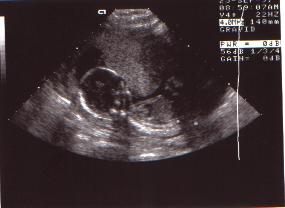

Vår älskade lille kämpe